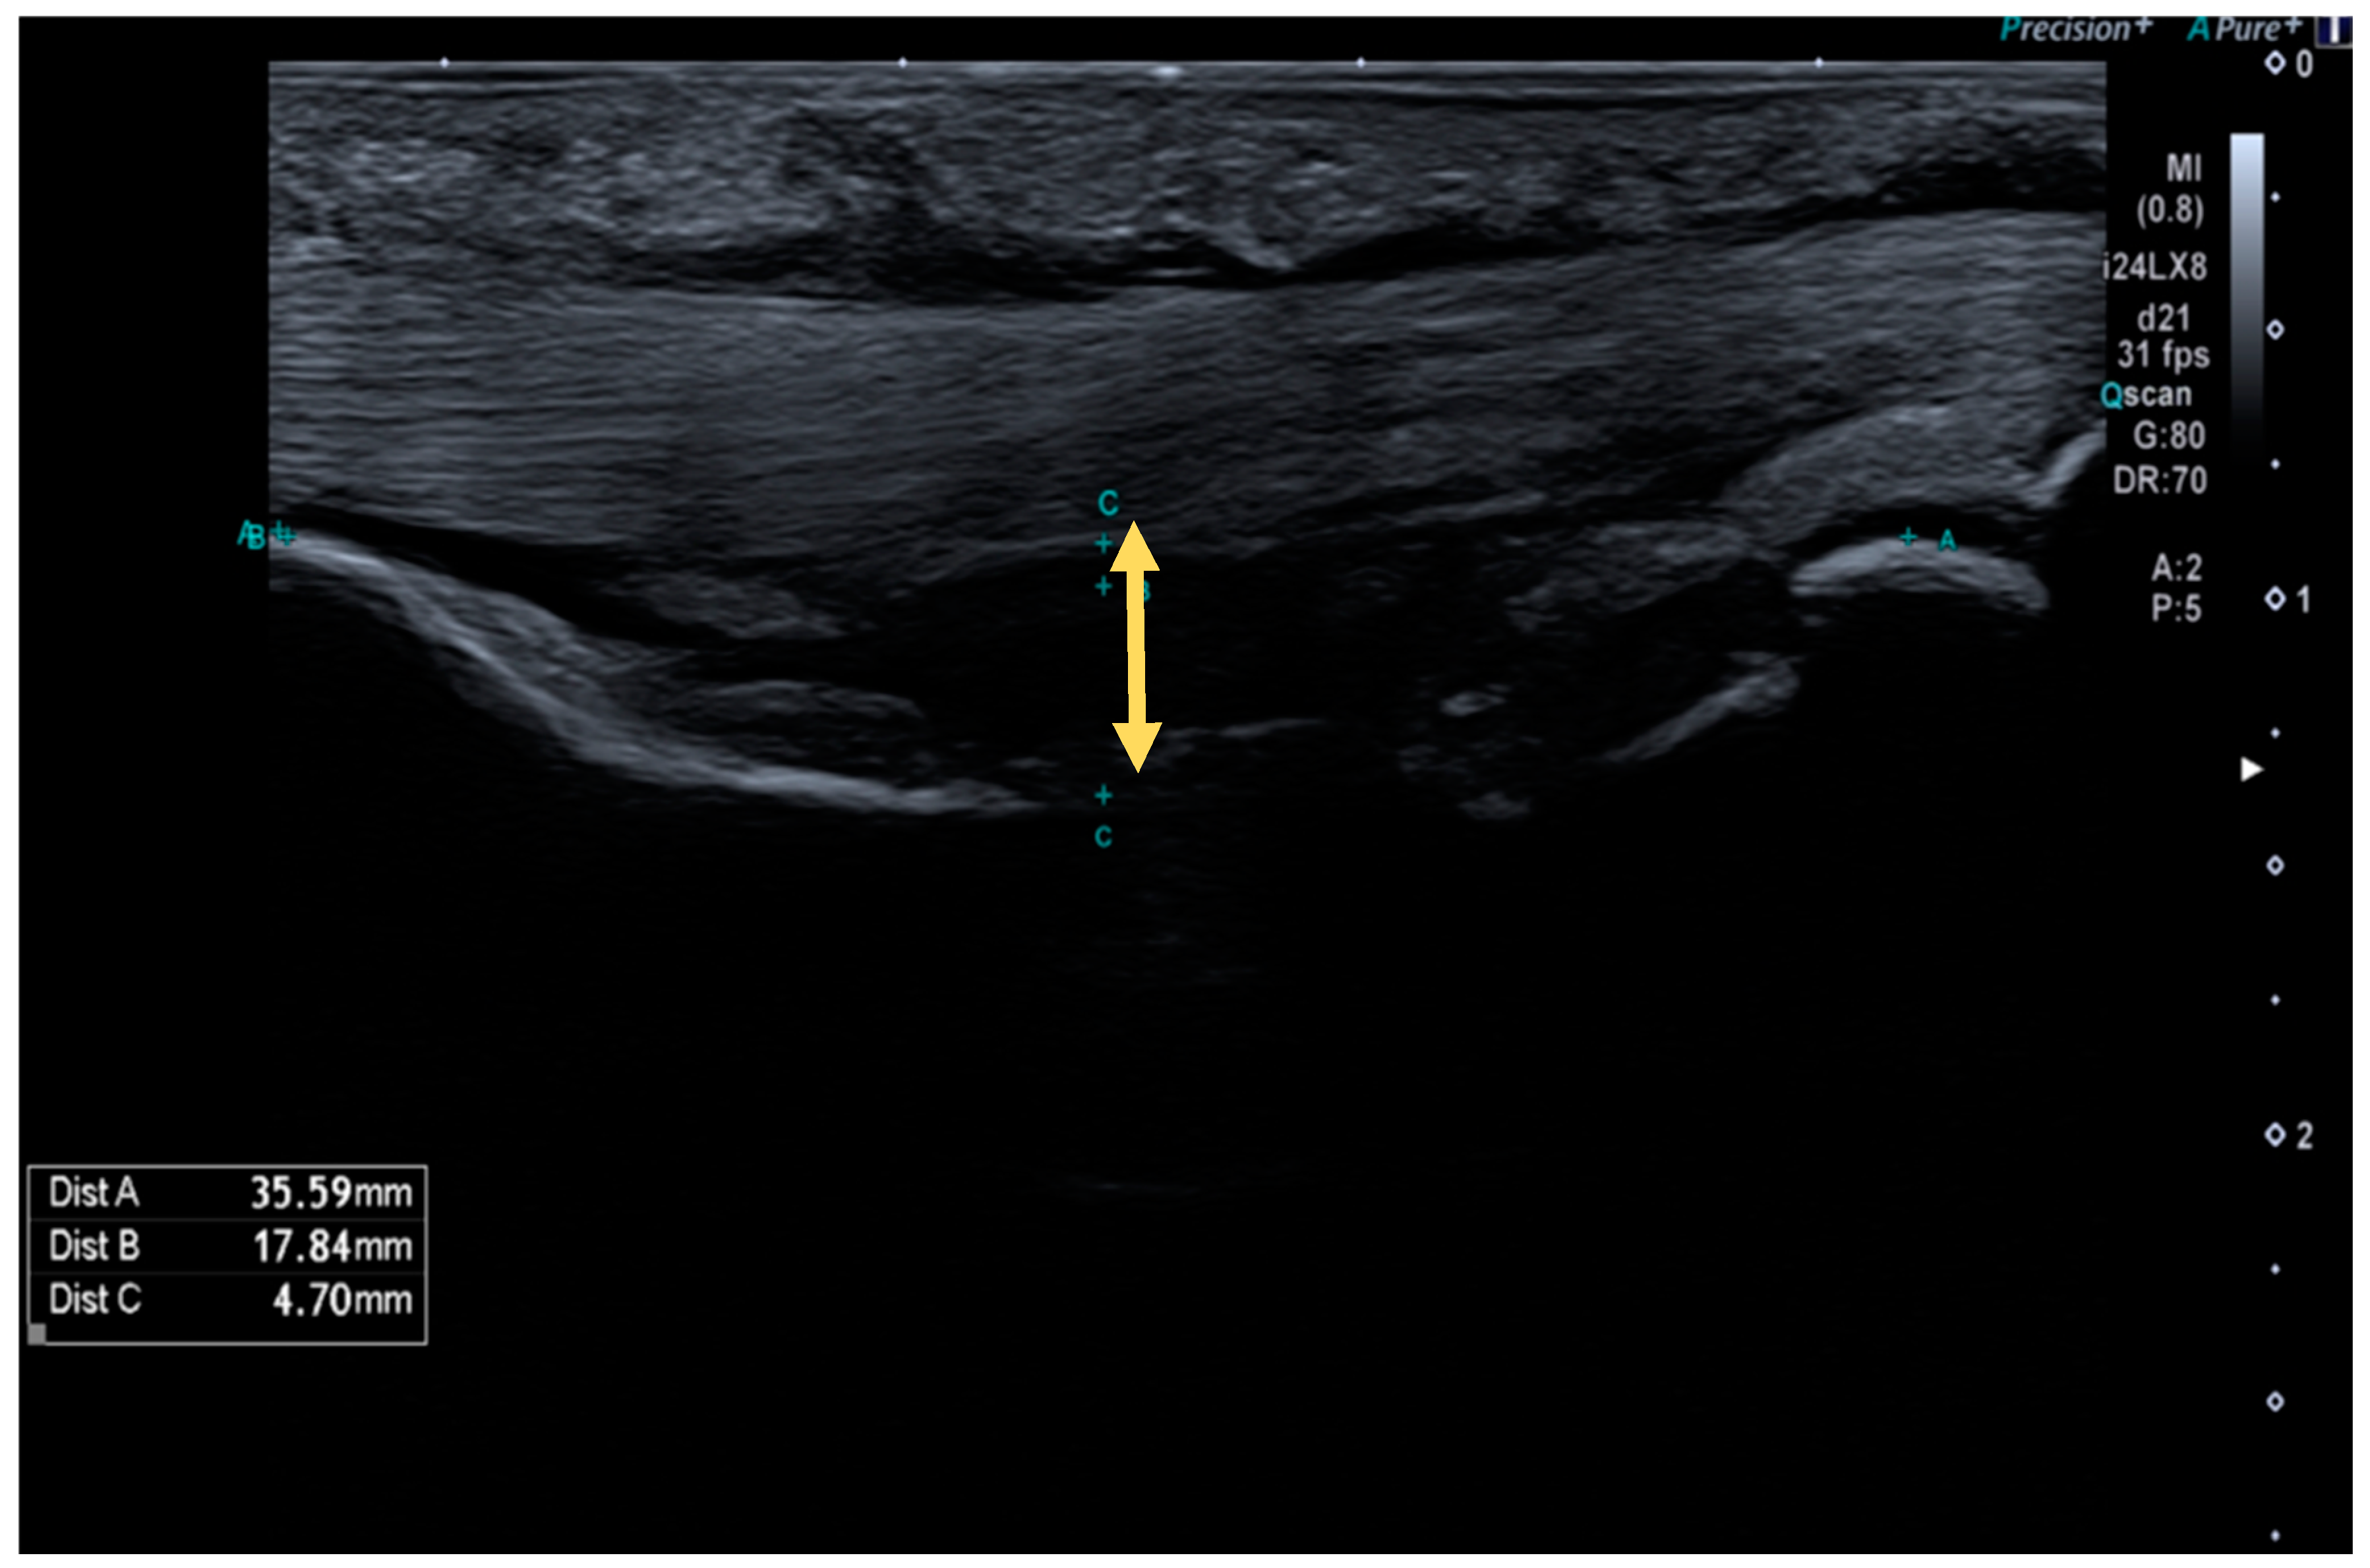

TBD was measured using a Canon Aplio i800 (Canon Medical Systems S.A., Madrid, Spain) equipped with a 24 MHz linear transducer (Figure 1).

High-resolution ultrasound image of a complete A2 pulley rupture. The arrow indicates the tendon–bone distance (TBD) in the midpoint of the proximal phalange.

Measurements were performed in the longitudinal axis on the level of the injured pulley (A2 or A4, 3rd or 4th fingers) and on the contralateral finger at the same level as a control, in order to calculate the TBD increase percentage. A TBD > 2 mm was considered a positive ultrasound test, while a TBD < 2 mm was considered a negative ultrasound test. To perform such measurements, the finger studied was positioned at a neutral metacarpophalangeal joint position, with 40° of proximal interphalangeal joint flexion and 10° of distal interphalangeal joint flexion. During the evaluation, the ultrasonographer performed a counter-resisted isometric flexion maneuver until maximum TBD was achieved. As it has been proposed in literature, the anatomical landmarks to systematize the measurement point were the middle point of the proximal phalanx for A2 measurements, and the middle point of the middle phalanx for A4 pulley measurements [6].